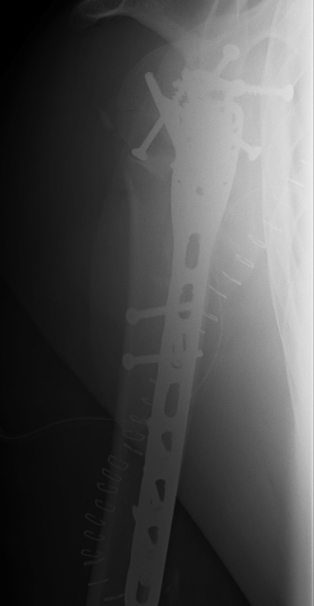

proximal humerus fracture Background ORIF with locking plate Arthroplasty Greater tuberosity fractures Lesser tuberosity fractures / avulsions Book traversal links for Proximal humerus fractures ‹ Pectoralis Major Tears Up Background ›